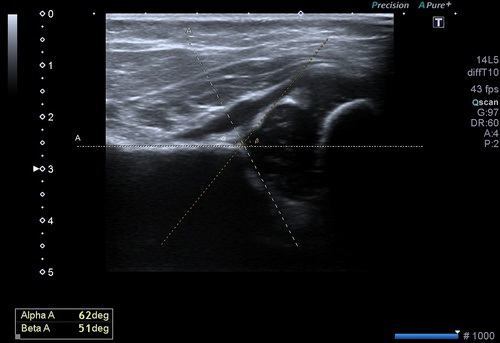

Bu inceleme de amaç her iki kalça eklemini oluşturan kemik yapıların, eklem ilişkilerinin ve kemik açılarının ölçülmesidir. Bu ölçümler ile kalça gelişiminin normal olduğu, yavaş olup düzelme eğilimi olacağı ya da gelişim geriliği olduğu saptanır. Bu ölçümlerin optimizasyonu için uluslararası bir sınıflama sistemi kullanılır.